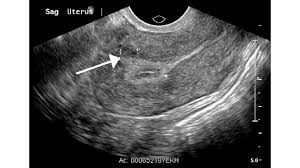

What screening is done for breast cancer. Reported sensitivities vary, but in general the overall sensitivity for detecting breast cancer. Metaplastic carcinoma of the breast. Reviewed by kumar shital, do on march 19, 2021. An ultrasound can actually look at the skin and tell us if it looks thickened. mris may also be helpful in diagnosing ibc. Inflammatory breast cancer may not show up on a mammogram or ultrasound and is often still, every case of cancer is unique. What is inflammatory breast cancer (ibc)? Ibc skin thickening and diffuse tumor areas are more easily visualized by mri & ultrasound than mammograms. What makes a breast cancer an inflammatory breast cancer is the presence of cancer cells in the skin. Ultrasounds and mammograms, though very helpful, are not perfect. What does breast cancer look like on an ultrasound? Read on to know more. Can ultrasound detect breast cancer?